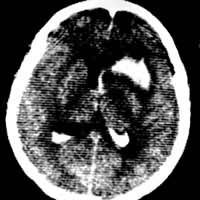

ÄÔÁö£¬70¡«80£¥¿ÉÓÉCT×÷³ö¶¨ÐÔÕï¶Ï¡£¼¸ÖÖ³£¼ûÄÔÁöµÄµäÐÍCT±íÏÖÈçÏÂ:ÐÇÐÎϸ°ûÁöΪÄÔÄÚµÍÃܶÈÖ׿飬¢ñ¡¢¢ò¼¶Õ߽߱çÇå³þ£¬ÎÞÇ¿»¯£¬¢ó¡¢¢ô¼¶Õߣ¬ÂÖÀª²»Õû£¬Óв»¾ùÔÈ»ò»·×´Ç¿»¯£¨Í¼1£©£»ÄÔĤÁö³Ê±ß½çÇå³þ¡¢ÃܶȾùÔȵĸßÃܶÈÖ׿飬ÒÔ¹ã»ùÓë¹ǻòӲĤÏàÁ¬£¬ÓоùÔÈÇ¿»¯£¨Í¼2£©£»´¹ÌåÖ×ÁöΪ°°ÉÏÃܶÈÂԸߵÄÖ׿飬ÓоùÔÈÇ¿»¯£»ÂÑʹÜÁöΪ°°ÉÏ»ìÔÓÃܶȲ¡±ä£¬Óв»¾ùÔÈÇ¿»¯;ÌýÉñ¾ÁöΪÇÅÄÔСÄԽǵͻòµÈÃܶÈÖ׿飬ÓëÔö´óµÄÄÚ¶úµÀÏàÁ¬£¬ÓоùÔÈÇ¿»¯¡£Ð¡ÌýÉñ¾ÁöÓÚÄÔ³ØÔìÓ°CTÉϿɼûСµÄÓëÄÚ¶úµÀÏàÁ¬µÄÖ×¿é£»×ªÒÆÁö³£³ÊƤÖʼ°Æ¤ÖÊÏÂÇø¶à·¢½á½ÚÐÔ²¡±ä£¬ÓÐÃ÷ÏÔµÄÄÔË®Ö×Î§ÈÆ£¬³Ê¾ùÔÈ»ò²»¹æÔò»·×´Ç¿»¯¡£